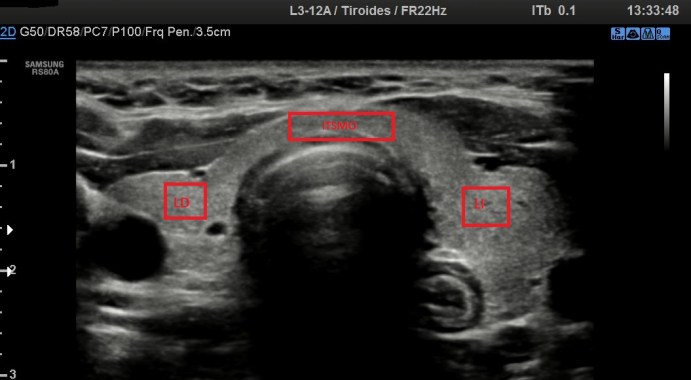

36. Protocolo de Tiroides. Los Cortes.

Ahora vamos a ver los cortes, no el protocolo, los cortes, es decir, como tenemos que manejar el transductor para realizar un protocolo de Tiroides normal.

Los cortes de los lóbulos y el Istmo son en transverso y en logitudinal, es decir, axiales al cuello y sagitales a éste.

Cada lóbulo será estudiado individualmente en transverso y longitudinal y siempre siempre colocados perpendicularmente a la estructura. El cuello no es plano, desde el cartílago a los laterales, el cuello se inclina, por tanto tendremos que inclinarnos nosotros con nuestra sonda para buscar el lóbulo de cada lado.

El Istmo es central, por tanto debemos apoyar la sonda central  transverso y en longitudinal, teniendo mucho cuidado porque el istmo es muy pequeño y cogerlo en longitudinal puede hacerse complicado al principio ya que además, tenemos que estar apoyando sobre la tráquea que es un superficie muy inestable.

Corte tranverso

En este caso realizamos un corte transverso del lóbulo derecho que es un corte axial del cuello, adecuándonos a la posición del lóbulo.